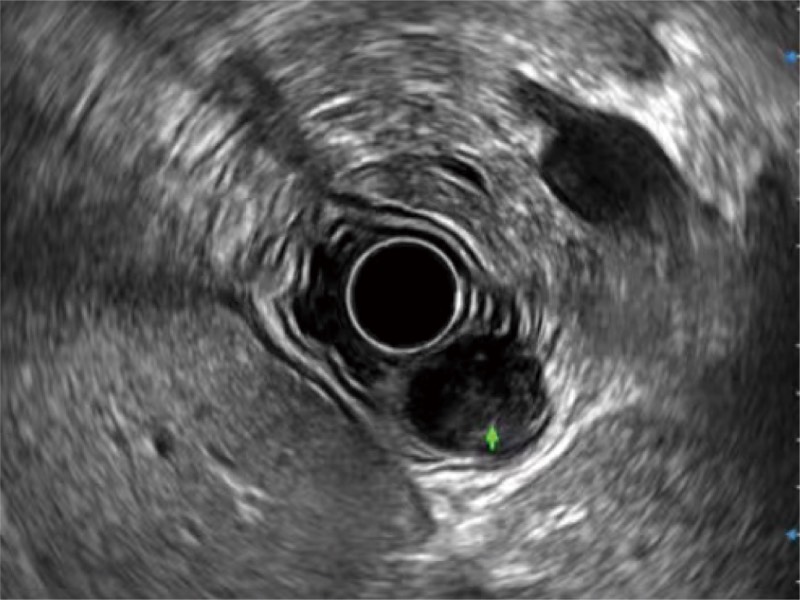

食管内间质瘤清晰显像